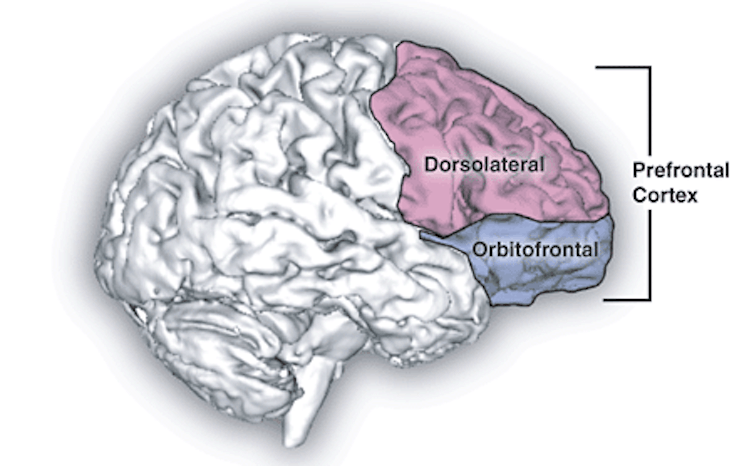

En utilisant cette approche, des expérimentations ont montré que le passage d’un sommeil REM non lucide à lucide était associé à une activité accrue des zones frontales du cerveau. De façon significative, ces aires sont associées à des fonctions cognitives « supérieures » comme le raisonnement logique et le comportement volontaire qui sont classiquement observés uniquement en état d’éveil. Le type d’activité cérébrale enregistrée, des ondes gamma, est connu pour signaler différents aspects de l’expérience humaine ; les sensations, émotions, pensées et mémoires sont “liées” ensemble dans la perception d’une conscience intégrée. Une étude de suivi a indiqué qu’une stimulation électrique de ces zones provoquait une augmentation du degré de lucidité vécu pendant un rêve.

Une autre étude a plus spécialement examiné les régions du cerveau impliquées dans les rêves lucides, et a montré une activité accrue dans des régions comme le cortex préfrontal et le précunéus (face interne du lobe pariétal, dans le cortex). Ces zones sont associées, là encore, à des savoir-faire cognitifs dits supérieurs comme le traitement des pensées autoréférentielles, faisant supposer que le rêve lucide est un stade hybride de la conscience.